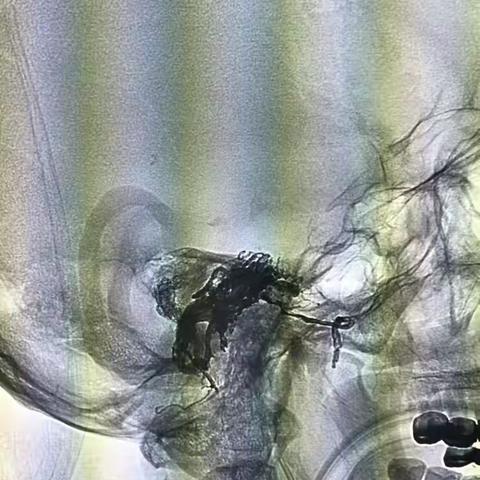

白玉新,女,60岁,基底动脉分支动脉瘤+AVM